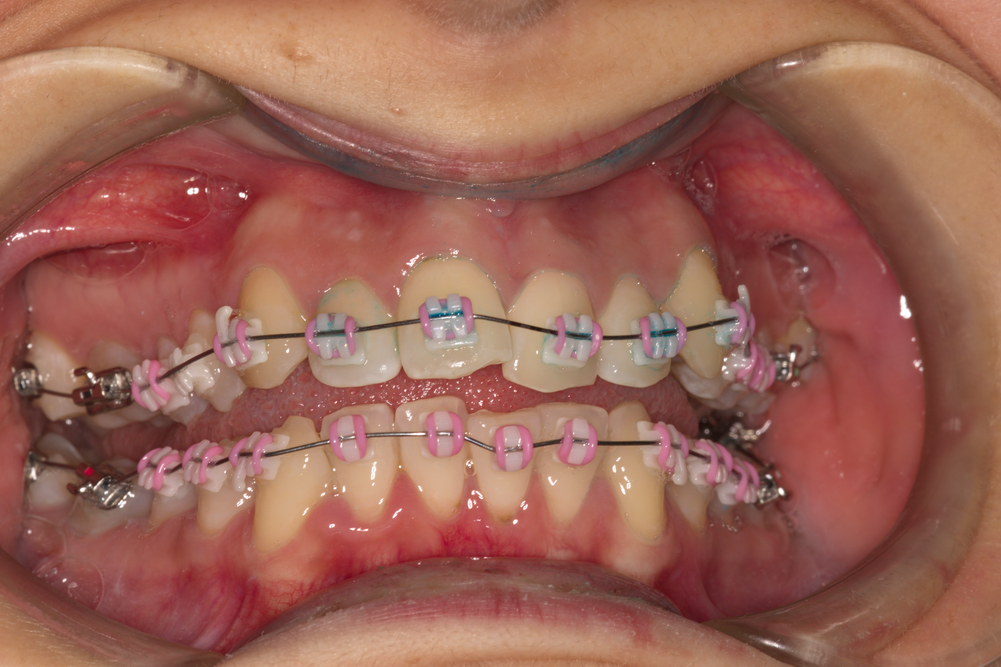

Начало на ортодонтското лечение на пациентката - фиксирани са брекети от серията COBY на YDM - Япония и никел - титанови кръгли дъги 0.14. Липсва лигатура на първи горен премолар вдясно